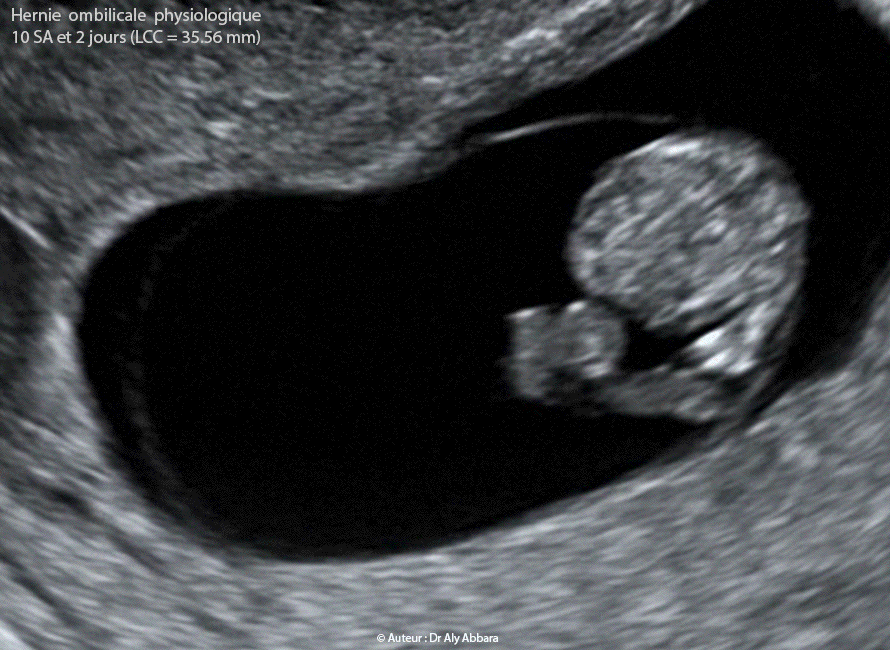

Hernie ombilicale physiologique du premier trimestre de la grossesse - Physiologic umbilical hernia - Physiologic Gut Heriation

Images échographiques et séquence vidéo montrant une grossesse intra-utérine évolutive de 10 SA et 2 jours (Longueur Crânio-Caudale "LCC" = 35,56 mm) caractérisée par la présence d'une hernie ombilicale physiologique disparaissant lors du contrôle échographique à 12,5.

• Il s'agit d'une formation échogène d'un diamètre largement inférieur à celui du périmètre abdominal ; elle est visible au niveau de la base du cordon ombilical, à son insertion sur la paroi abdominale antérieure.

Cette formation contient une petite partie des anses digestives, et évolue au sein de la base du cordon ombilical.

• L'évolution ultérieure confirme le caractère physiologique de cette hernie ombilicale, parce que le contrôle échographique réalisé à 12,5 SA montre sa disparition totale.